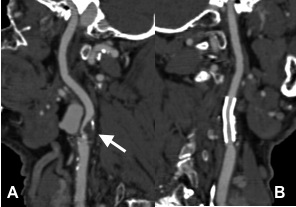

Abbildung:

Abbildung A zeigt eine CT Angiographie der rechten Nierenarterie bei einer jungen Patientin mit schlecht einstellbarem Bluthochdruck. Die CTA zeigt deutlich eine hochgradige Abgangsstenose der rechten Nierenarterie (Pfeil). Anhand dieser CT Angiographie wurde die Entscheidung zur PTA und Stentimplantation getroffen, und die Behandlung wurde geplant.

Abbildung B zeigt die Angiographie unmittelbar vor der Stentimplantation, welche den CT-Befund bestätigt (Pfeil).

Abbildung C zeigt die Kontrollangiographie nach Stentimplantation (Pfeil) mit hervorragendem Ergebnis.